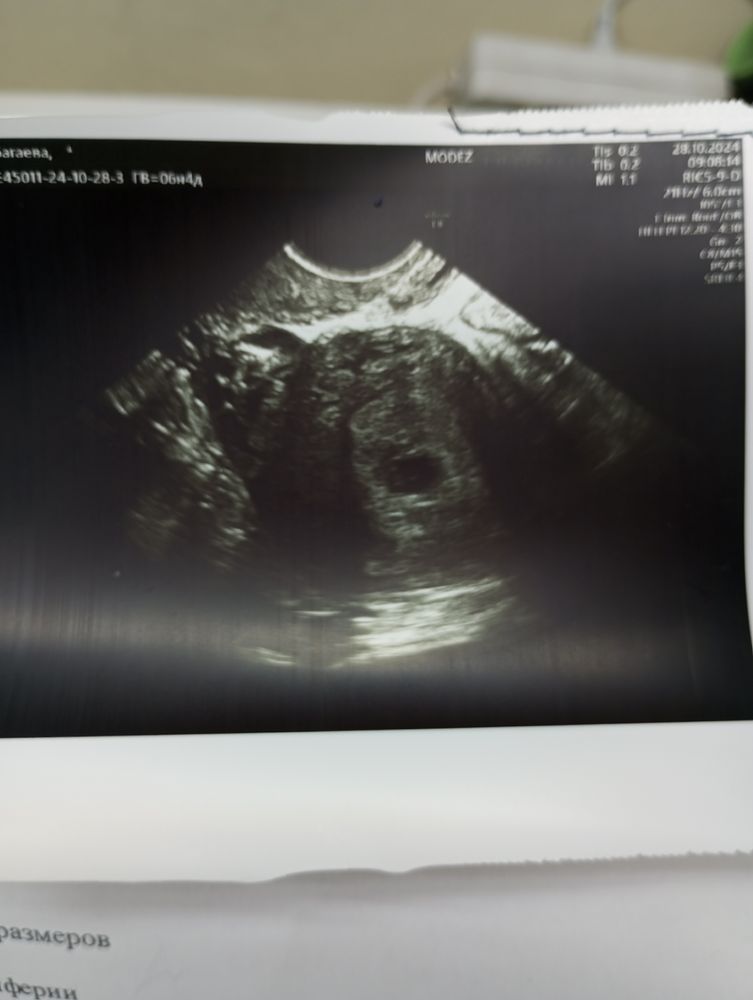

Очень маленькое пя для срока,средний внутренний диаметр получается 5,6 мм,поздняя овуляция не при чем,у вас же на 29 д.ц электронный показал 2-3 недели,а с поздней овуляцией на 20-21 д.ц,на 29 д.ц 8-9 дпо только и тесты вообще отрицательные ещё,а у вас уже даже не 1-2 было,а 2-3,значит овуляция точно нормальная была, электронный срок от зачатия показывает,а маленькое пя,потому что хгч плохо растет и маленький для срока,от его роста и зависит размер пя,да и в норме такое пя в 5 недель и в нем нет ещё никакого эмбриона,а у вас появился,потому что срок 6+ недель,но при нормальной беременности разница между пя и ктр должна быть больше 5 мм,а у вас пя 5 мм,а эмбрион 1 мм,что тоже плохо, разница 4 мм, развиваться некуда ему в таком пя,хгч сдайте повторно

А 5,5 недель вам поставили по размеру эмбриона,а плодное на 5 недель

Ксения , у меня получается что по ужи 5.5 а плодное яйцо 5х5х7

А не маленькое ли пя для такого срока? Или овуляция была поздняя?